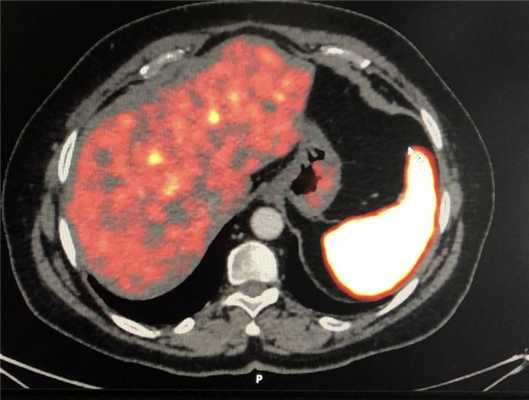

• Метастазы в печени и вторично измененные лимфатические узлы выглядят так же, как первичная опухоль, и являются гиперваскулярными:

о Чаще всего метастазы выявляются в печени, лимфоузлах возле опухоли, а также в костях (склеротического характера)

о Уровень «жидкость-жидкость» в метастазах эндокринных опухолей в печени описывается как специфический признак

(Слева) На аксиальной КТ с контрастным усилением у пациента с нейроэндокринной опухолью визуализируются множественные метастазы в печени с уровнями «жидкость-жидкость». Наличие уровней жидкости описывается как специфичный, хотя и нечасто встречающийся, признак метастазов нейроэндокринных опухолей в печени.

(Справа) На аксиальной КТ с контрастным усилением визуализируется гиперваскулярное объемное образование в хвосте поджелудочной железы, сопоставимое с нейроэндокринной опухолью. Обратите внимание, что крупный метастаз в печени накапливает контраст примерно так же, как первичная опухоль в поджелудочной железе. (Слева) На аксиальной КТ с контрастным усилением определяется НЭО поджелудочной железы, прорастающая в воротную вену. Виден также крупный метастаз в печени. Паллиативное лечение (химиоэмболизация) дает возможность на несколько лет облегчить состояние пациента. Злокачественные НЭО часто прорастают в воротную вену и метастазируют в печень.

(Справа) На аксиальной КТ в артериальной фазе контрастного усиления в печени визуализируются многочисленные гиперваскулярные метастазы первичной НЭО поджелудочной железы. Первичная опухоль и ее метастазы, как наблюдается и в этом случае, часто представляют собой образования с повышенной васкуляризацией, обнаруживаемой в артериальной фазе. (Слева) На аксиальной КТ с контрастным усилением (объемный рендеринг) у пациента с подозрением на инсулиному визуализируется гиперваскулярное объемное образование в головке поджелудочной железы.